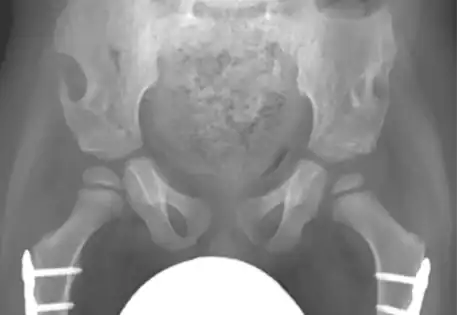

Hip dysplasia can manifest in various syndromes, including Prader-Willi syndrome, arthrogryposis, caudal regression syndrome, and Kabuki syndrome. Syndromic hip dysplasia cases in Dubai often involve more pronounced anatomical distortions, posing greater challenges in treatment and higher recurrence risks. Dr. Qureshi, a child orthopaedic doctor in Dubai, is experienced in addressing these complex cases, providing specialised care and management for each unique condition.

Dr. Qureshi has successfully managed numerous cases of syndromic hip dysplasia, employing investigations such as arthrography and CT imaging to assess reconstruction feasibility and plan surgical interventions. The treatment strategy is customarily crafted as a tailored combination of different techniques to address distinct components and contributory factors contributing to the dislocation.